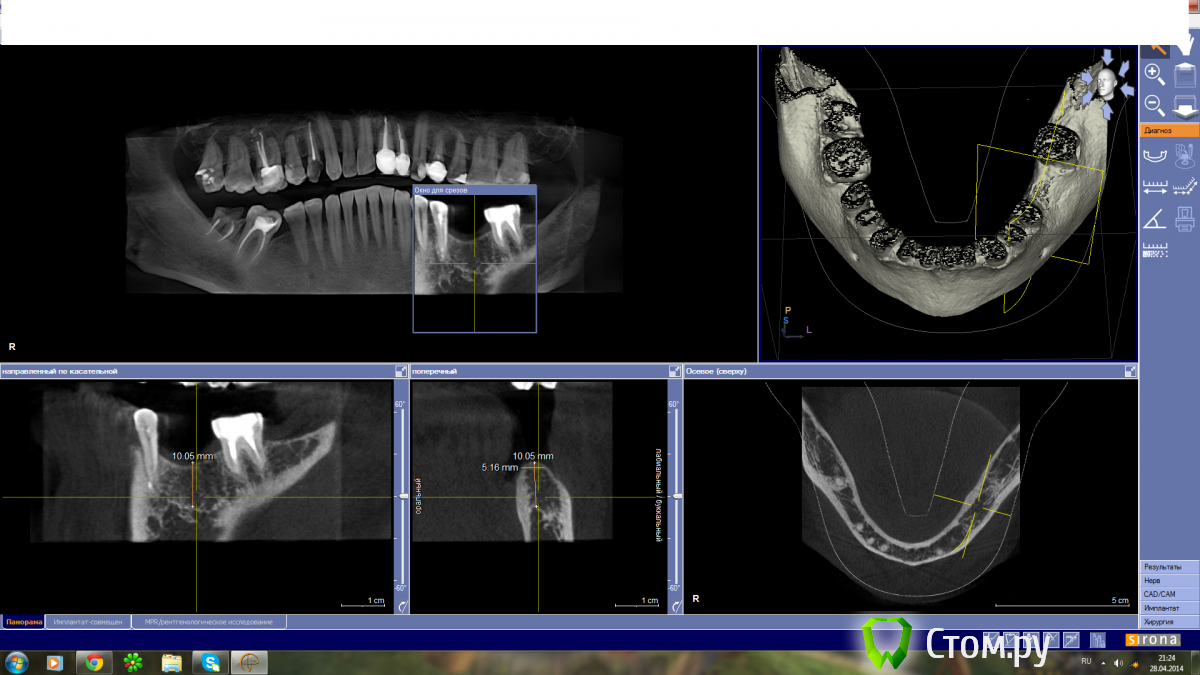

Milanomoda Опубликовано 28 апреля, 2014 Поделиться Опубликовано 28 апреля, 2014 Имеется пациент с жалобой на адентию в области 36. Вот что имеем на снимках:чтобы оставить стандартный имплант 3.75x10 в данном случае нужно провести как горизонтальную так и вертикальную аугментацию нч...Какой вид аугментации тут будет предпочтительнее ? сам склоняюсь к аугментации костными блоками. Ссылка на комментарий

Alexey Doc Опубликовано 28 апреля, 2014 Поделиться Опубликовано 28 апреля, 2014 Возможно я ошибаюсь , но мне кажется что нижней границей вашего измерения является не стенка нижнечелюстного канала.Выложите панорамную реконструкцию нижней челюсти в которой срез проходит через н.ч каналы 2 Ссылка на комментарий

red_butler Опубликовано 28 апреля, 2014 Поделиться Опубликовано 28 апреля, 2014 Срезы не правильно выставлены, отсюда ошибка с замерами. Посмотрите на правую сторону и на ментальное на 3d реконструкции, переставьте срезы, возможно в просмотрщике можно нижне-челюстной канал выделить, и все встанет на свои места 2 Ссылка на комментарий

MayTaraki Опубликовано 28 апреля, 2014 Поделиться Опубликовано 28 апреля, 2014 (изменено) Канал ниже находится даже на тех срезах что есть это видноМожно отталкиваться от ментального отверстия... Точка выхода видна между 34 и 35А вообще не мешало бы пройти обучение по чтению кт ... У сироны с этим не плохо Изменено 28 апреля, 2014 пользователем MayTaraki Ссылка на комментарий

kriokov Опубликовано 28 апреля, 2014 Поделиться Опубликовано 28 апреля, 2014 А как правильно срезы выставлять?так хотя бы, + аксиальный срез на уровне верхушек зубов или канала Ссылка на комментарий